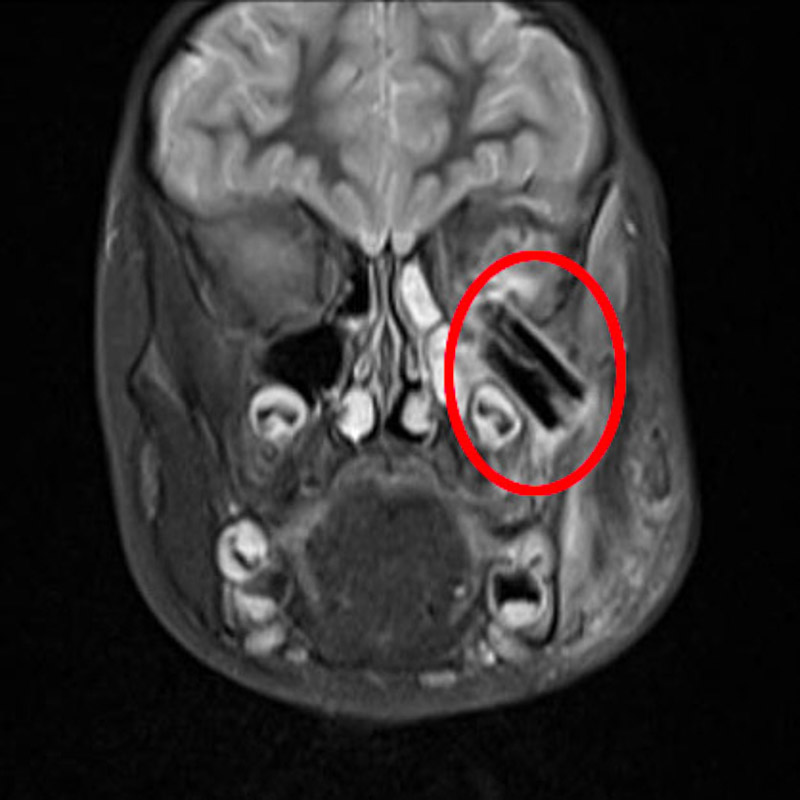

接診醫生得知患兒曾摔跤受傷,便推斷傷口可能有異物殘留,立即安排其入院進行詳細檢查。檢查發現樹枝從面部直插顳下窩至眼球后方,還有零星碎片斷在顱底,導致眼球位移,面頰部、鼻部、眼部感染,情況不容樂觀。

術中,口腔頜面外科團隊自面部將原傷口切開,見大量膿液噴涌而出,傷口深,視野差,大大增加了異物取出的難度,如果異物清除不干凈,會導致創口內持續發炎,導致二次手術。

術者順著樹枝刺入的方向,小心翼翼分離周邊組織,將多片長達3厘米的樹枝殘留物取了出來,經過兩個多小時,順利將傷口內異物全部清除并縫合還原。術后患者平安返回病房,醫護人員給予患者抗炎、消腫、補液、換藥等對癥支持治療,目前,患兒已成功出院。